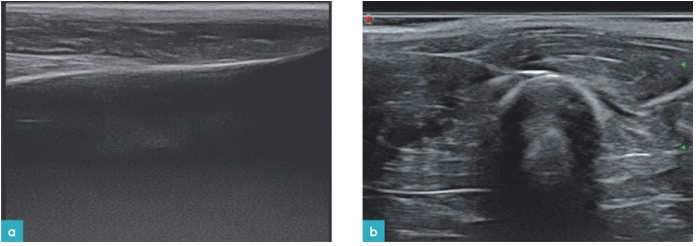

软骨下骨超声影像为高回声表面伴后方声影,不同骨骼的软骨下骨的超声表现均为不同。紧贴骨质表面的透明软骨为无回声暗区。滑膜为低回声带,与骨骼相接的部位呈高回声的点状区域。滑膜囊为高回声的线状物,在与肌肉的连接点处,二者的回声融合在一起(图5)。